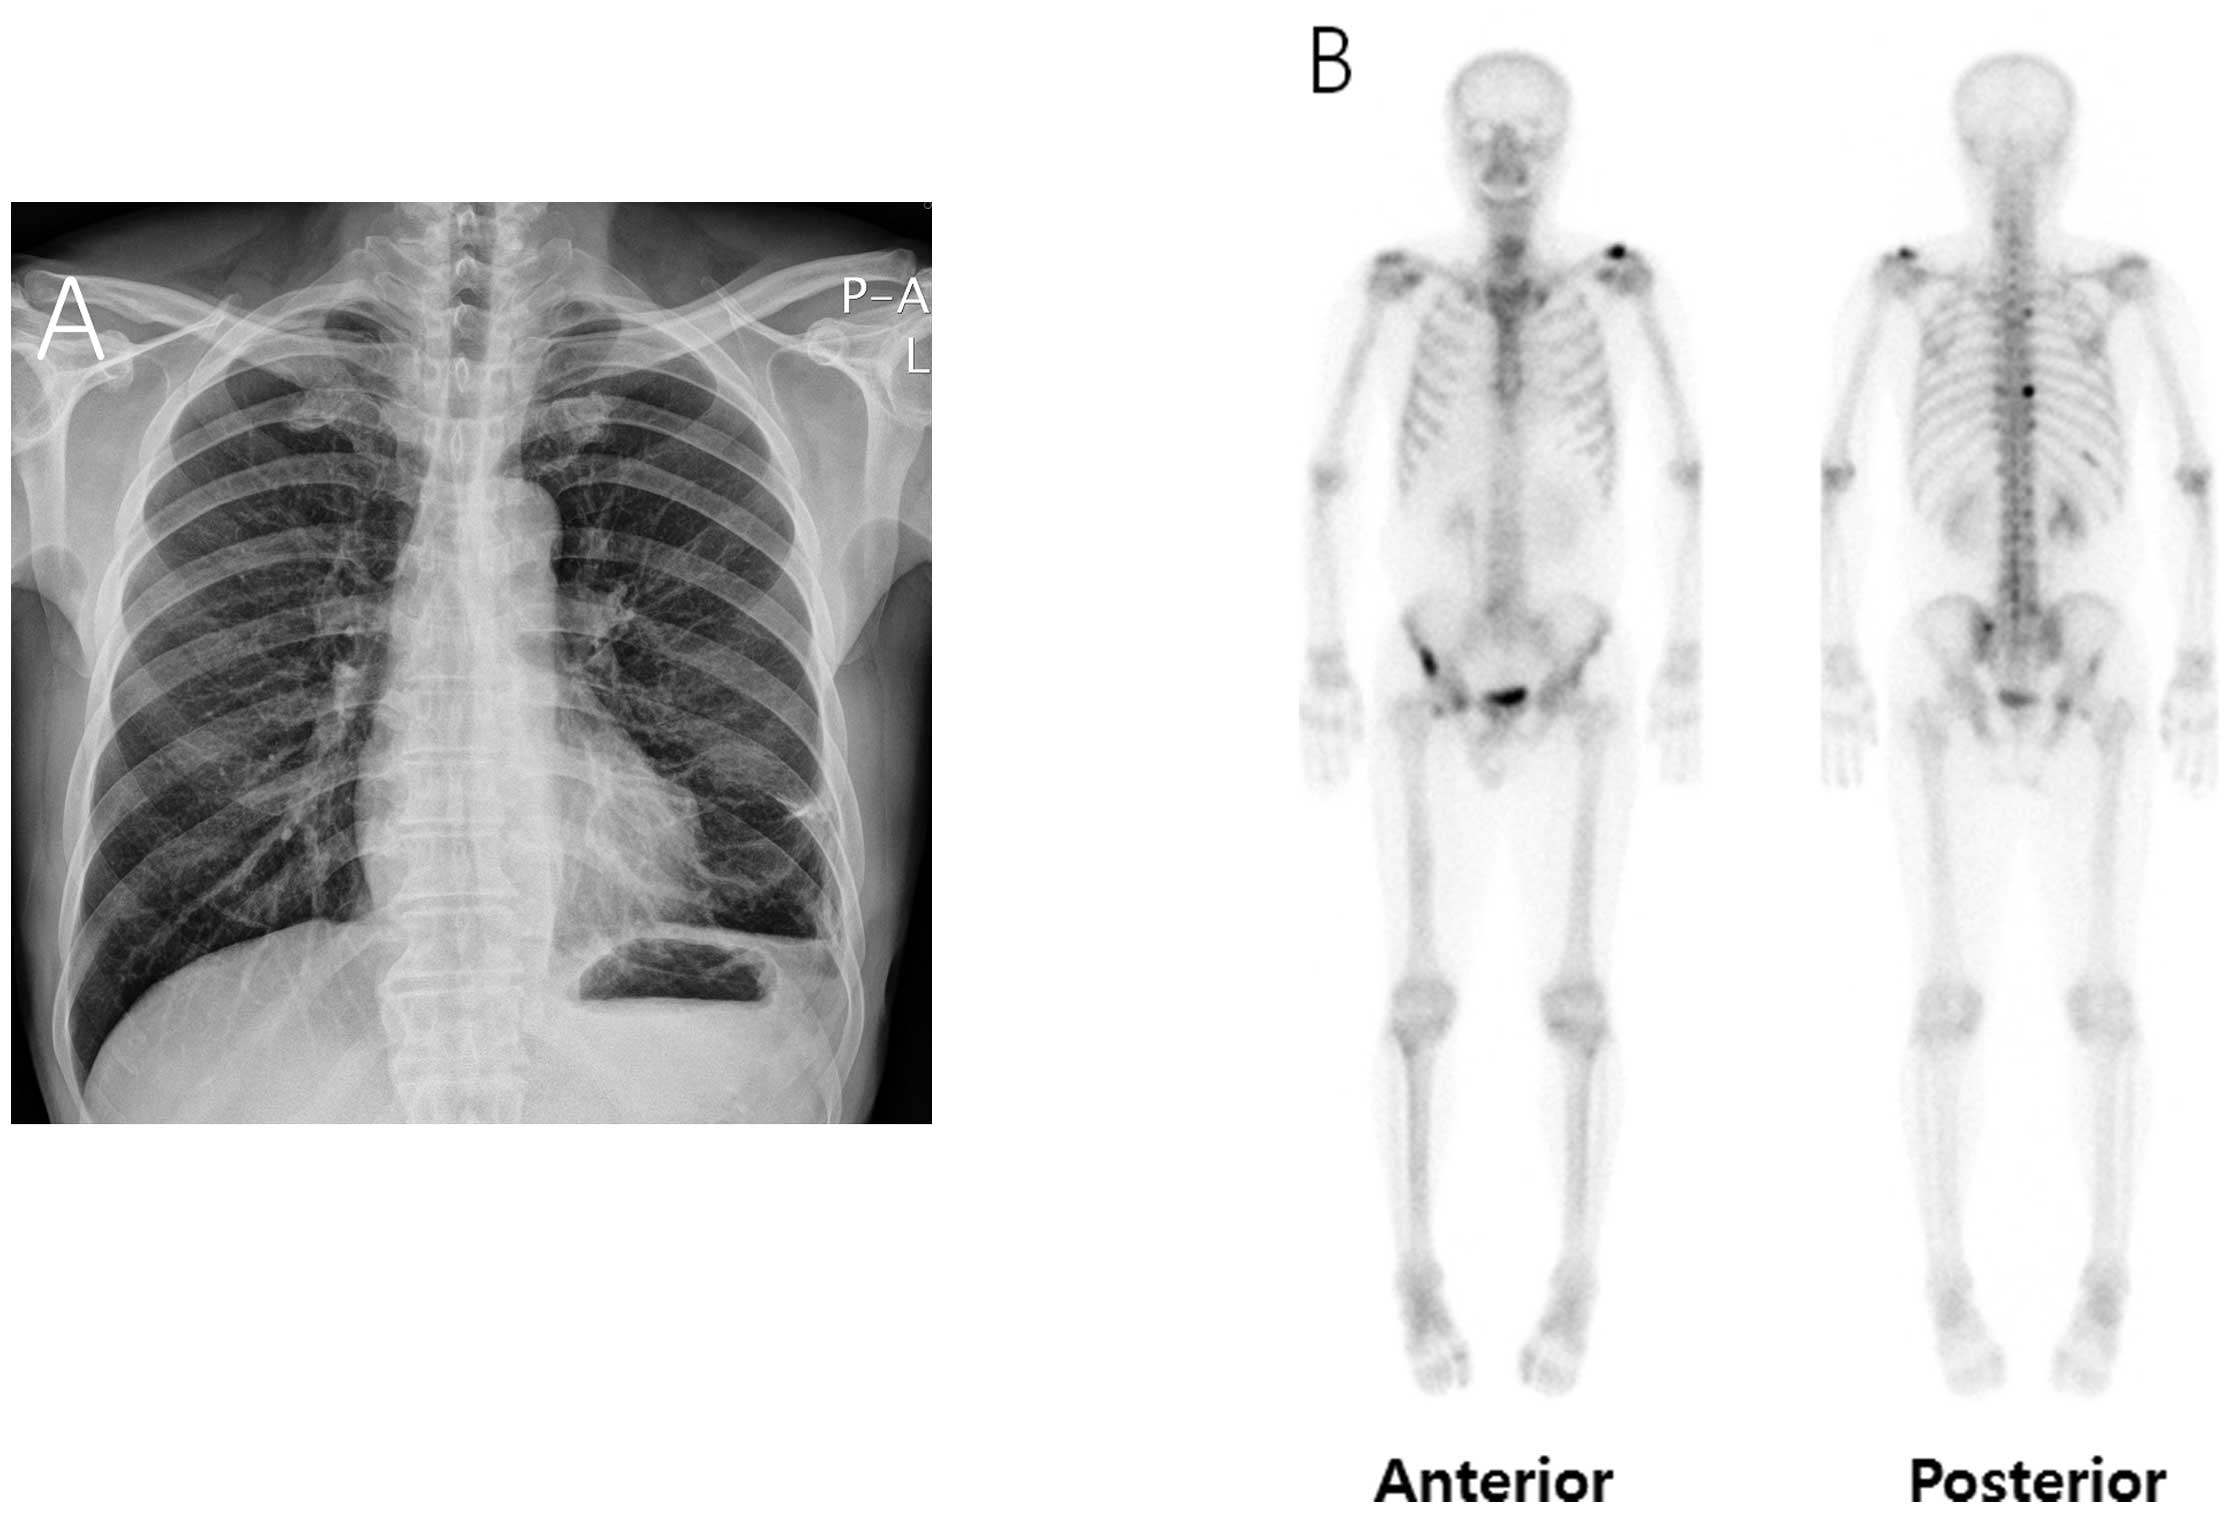

A prostate biopsy revealed adenocarcinoma of the prostate gland. A bone scan was performed for staging, which revealed multiple bone metastases (Fig. 1D). Therefore, the chylothorax was considered to have resulted from thoracic duct obstruction by enlarged lymph node metastasis from prostate cancer. Androgen deprivation therapy (ADT) was initiated, with simultaneous administration of goserelin and anti-androgen. After 3 months, the amount of pleural effusion had decreased (Fig. 2A) and the serum PSA level decreased from 194.6 to 31.68 ng/ml following ADT. A bone scan performed 8 months after the initiation of ADT revealed that the intensities of multiple bone uptakes had decreased significantly when compared to the initial scan (Fig. 2B). The patient is undergoing regular follow-up at our outpatient clinic for 1 year after diagnosis and has not reported experiencing any further discomfort.

Figure 2.

(A) Chest radiography and (B) bone scan at 3 and 8 months after initiation of androgen deprivation therapy, respectively. THE chest radiography image showS disappearance of the previous left pleural effusion. The intensities of the multiple bone metastases are decreased on the follow-up bone scan.